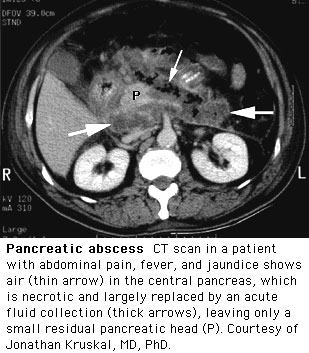

A fifty-six year old, slightly obese female presents to your clinic with complaints of nausea, epigastric pain, vomiting, and tenderness, which she describes as radiating or boring through her back for the past 24 hours. She reports she is not on any medications, does not use alcohol, has made no recent trips outside of the country and that her total cholesterol was elevated (greater than 200) on her last trip to the physician's office. On physical exam you note, that she is slightly tachycardic (110), BP - 100/60, and her temperature is 101.5. You note that she is slightly jaundiced and has slight abdominal distension. She has diminished bowel sounds, and on palpation she is tender but has no rebound pain and does not guard her abdomen. The physician you are working with suspects the patient is suffering from pancreatitis secondary to gallstones . The physician orders serum and urinary amylase, serum lipase, glucose, calcium levels, WBC , bilirubin, - all of which are elevated except for the calcium, which is lowered. In addition he orders an ultrasound and CT. The patient's CT demonstrated that some pancreatic tissue did not enhance with IV contrast - the physician informs you that this is indicative of necrotizing pancreatitis . The patient was referred to a surgeon and taken to the O.R. for surgical debridement and placed on antibiotics.